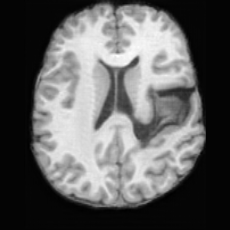

Pathology-to-Healthy Editing. Fig. 5 (a) presents comparison results on four input brain images with lesions of varying sizes, shapes, and densities. All competing models, although specialized for healthy brain image synthesis, struggle to reconstruct pathological regions, especially near lesion boundaries. In contrast, USB accurately reconstructs the corresponding healthy brain, even in challenging cases with large, high-density lesions where normal brain structures are almost completely obscured (last row). Tab. 2 provides a quantitative comparison for pathology-to-healthy editing, where USB achieves the best performance across all three datasets, demonstrating the effectiveness of its unified framework in reconstructing healthy brains from pathological inputs. Additional results are in Suppl. B.

Healthy-to-Pathology Editing. As shown in Fig. 5 (b), given a healthy brain image paired with a random lesion mask, USB seamlessly embeds the lesion into the healthy anatomy, producing realistic pathological appearances consistent with surrounding structural context. Yet UNA’s syntheses are visually unrealistic, with the conditioned lesion mask simply overlaid as a parallel layer onto the healthy brain. Tab. 3 further demonstrates USB’s superior performance. The evaluation was conducted on 100 pairs of lesion masks and healthy brains, with real stroke images

(a)PathologicalInput ImageSynthSR [18]Brain-ID [28]UNA [30]USBHealthyGround TruthRefer to captionRefer to captionRefer to captionRefer to captionRefer to captionRefer to captionRefer to captionRefer to captionRefer to captionRefer to captionRefer to captionRefer to captionRefer to captionRefer to captionRefer to captionRefer to captionRefer to captionRefer to captionRefer to captionRefer to captionRefer to captionRefer to captionRefer to captionRefer to caption(b)HealthyInput ImageConditionalLesion MaskUNA [30]USBRefer to captionRefer to captionRefer to captionRefer to captionRefer to captionRefer to captionRefer to captionRefer to captionRefer to captionRefer to captionRefer to captionRefer to captionRefer to captionRefer to captionRefer to captionRefer to caption

Figure 5: Comparison of bidirectional brain editing. (a) pathology-to-healthy, the circles and arrows highlight lesion regions and unsuccessful reconstructions; (b) healthy-to-pathology. Note that SynthSR and Brain-ID cannot perform healthy-to-pathology editing.